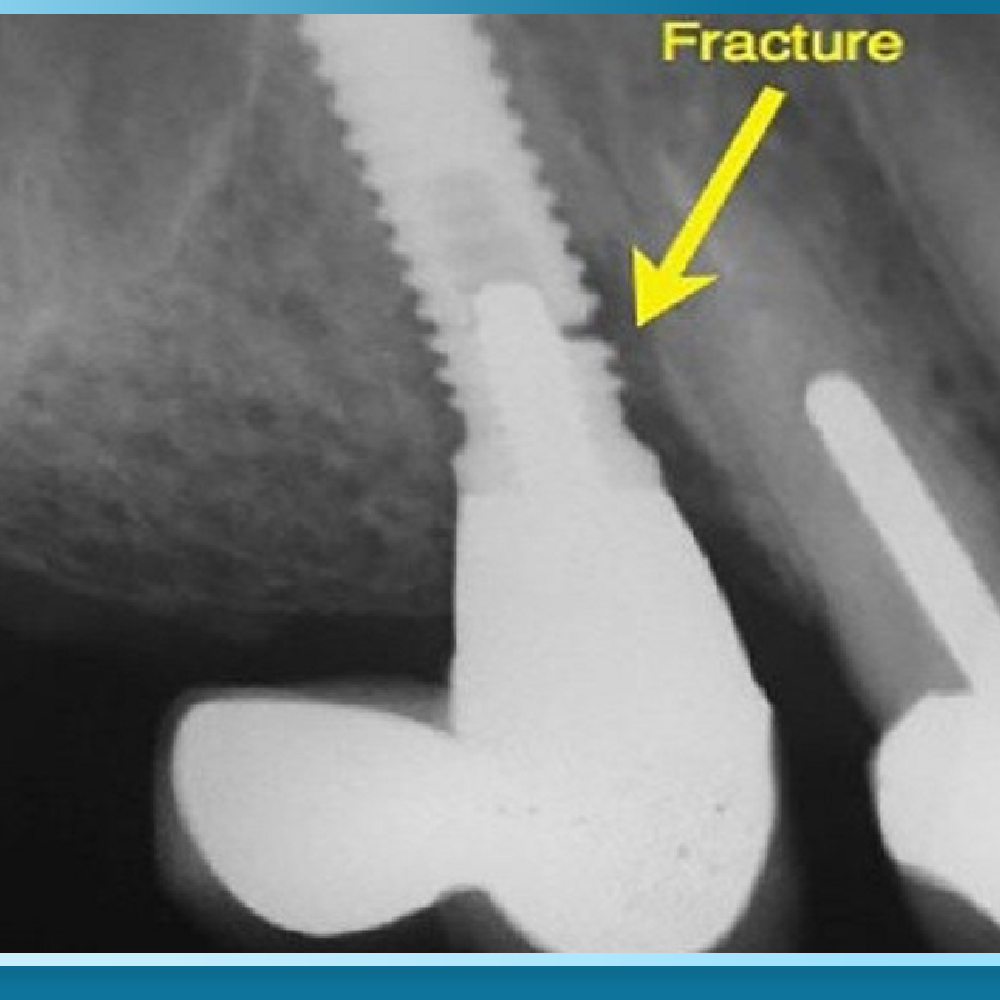

Trụ Implant có bị gãy sau nhiều năm sử dụng không?

Trường hợp gãy trụ Implant là cực kỳ hiếm gặp nếu sử dụng các dòng trụ Titanium chính hãng và được cấy ghép đúng kỹ thuật. Trụ chỉ có rủi ro bị gãy nếu vị trí đặt trụ bị sai lệch gây ra tình trạng quá tải lực nhai kéo dài hoặc bệnh nhân mắc chứng nghiến răng nặng mà không sử dụng máng bảo vệ.